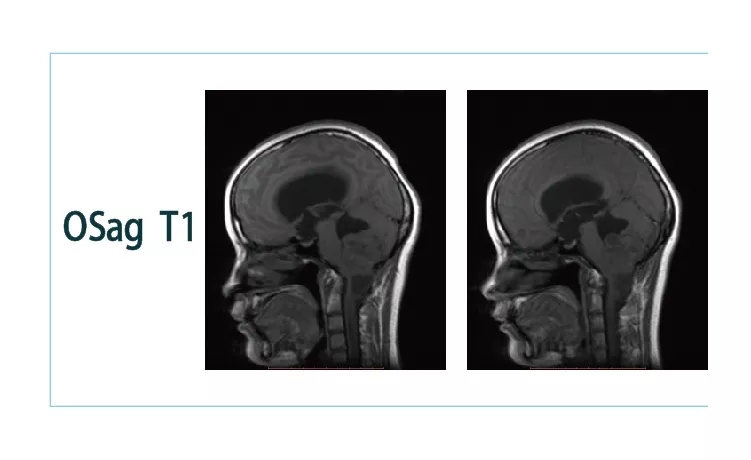

【朗润影像档案】20181026磁共振影像病例结果讨论